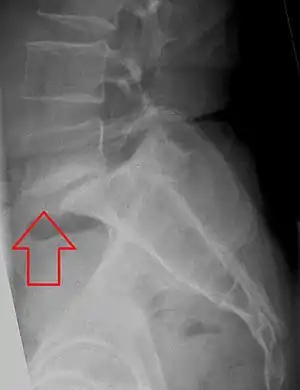

L5 S1 Spondylolisthesis Grade II with forward slipping of L5 on S1 <50% L5 S1 Spondylolisthesis Grade II with forward slipping of L5 on S1 <50%